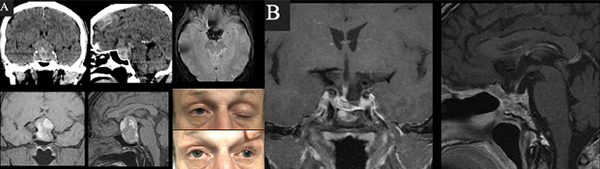

Se analizaron retrospectivamente las historias clínicas de 14 pacientes con diagnóstico de apoplejía hipofisaria intervenidos quirúrgicamente por vía endoscópica endonasal en un periodo de 7 años, comprendido entre enero de 2013 y diciembre de 2019, en dos Servicios de Neurocirugía de la Ciudad de Buenos Aires (uno público y uno privado). El diagnóstico de AH fue definido por un cuadro de cefalea súbita intensa, alteraciones visuales y disfunción adeno-neurohipofisaria, acompañado de estudios por imágenes que demuestren hemorragia/infarto de un tumor hipofisario y diagnóstico anatomopatólogico de adenoma2. Se clasificaron los pacientes según las guías del Reino Unido y el sistema de clasificación de Jho y col.8-9 Todos los pacientes fueron estudiados con tomografía computada (TC) de cerebro y resonancia magnética (RM) de hipófisis sin y con gadolinio y angio RM de vasos intracraneales, analizando las características tumorales, tiempo evolución del sangrado (Figura 1), utilizando la clasificación de Wilson-Hardy y Knosp10,11. Se recabaron los datos endocrinológicos clínicos y el panel hormonal completo pre y postquirúrgico, con dosaje de T4 (tiroxina) libre, TSH (tirotrofina), GH (hormona de crecimiento), IGF1 (factor de crecimiento insulino-símil tipo 1), ACTH (adrenocorticotrofina), cortisol, PRL (prolactina), LH (hormona luteinizante), FSH (hormona foliculoestimulante), estradiol (en mujeres) y testosterona (en varones). El hipopituitarismo fue definido como la deficiencia en al menos 1 de los ejes hipofisarios. Fueron investigados los posibles factores precipitantes de hemorragia. Se analizaron los exámenes oftalmológicos pre y postoperatorios, registrando los resultados del CV y AV de todos los pacientes.

Fig. 1. RM donde se visualizan los distintos estadios de hemorragia. A. Agudo: iso en T1 e hipo en T2. B. Subagudo: hiper T1 e hiper T2. C. Crónico hipo T1 e hipo T2, con nivel líquido.

Caso 1. A. Preoperatorio. Varón de 63 años, hipertenso y antiagregado con AAS que consultó por cefalea, náuseas, vómitos y síncope. Al examen físico presentaba disminución de la AV en ojo izquierdo + ptosis palpebral y midriasis izquierdas. En la TC y RM de cerebro e hipófisis se evidenciaba una lesión selar con componente hemorrágico y edema de la vía óptica. El CVC evidenciaba hemianopsia temporal izquierda y cuadrantopsia superior derecha. B. Postoperatorio. RM que demuestra resección completa y CVC normal.

Caso 2. A. Preoperatorio. Varón de 54 años que consultó por cefalea, náuseas y vómitos. Al examen físico presentaba disminución de la AV y III par completo izquierdo +. En la TC y RM de cerebro e hipófisis se evidenciaba una lesión selar-supraselar voluminosa con contenido hemático. B. Postoperatorio. RM que demuestra resección completa de la lesión.

Caso 3. A. Preoperatorio. Paciente de 31 años, anticoagulado por TEP derivado de otro hospital por disminución aguda de la visión. La RM de hipófisis evidenciaba una lesión selar-supraselar voluminosa con un gran contenido hemorrágico. El CVC objetivaba amaurosis derecha y hemianopsia izquierda. B. Postoperatorio. RM que demuestra resección completa de la lesión y CVC con mejoría parcial.